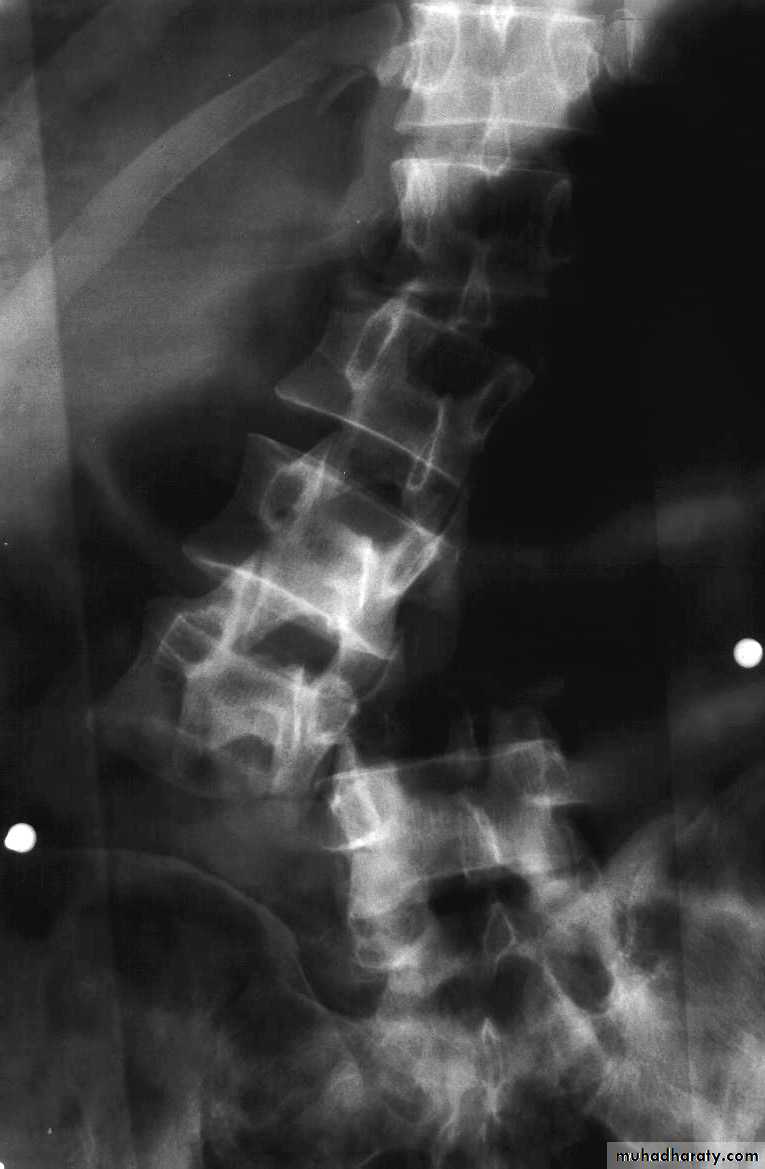

X-rays:

Cervical: 3 views.AP, lateral and open mouth.

Thoraco-lumbar: 2 views.

AP & lateral.

Flexion-Extension views.

Thoraco-Lumbar fractures

50% of injuries occur at Thoraco-lumbar junction.